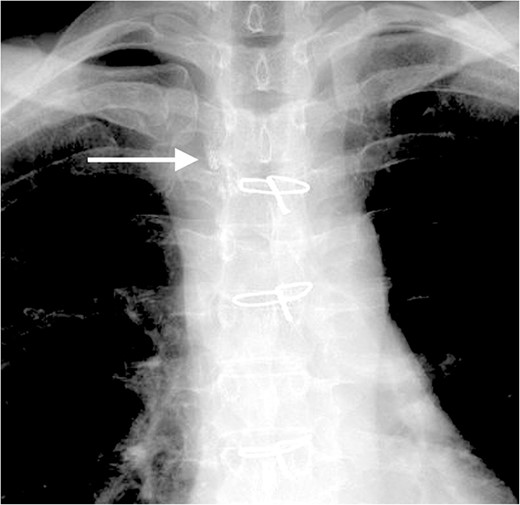

On post-operative day 17, she visited our hospital for a routine follow-up, and her chest X-ray revealed a massive right pleural effusion (Fig. 3). Therefore, she was re-admitted to our hospital and right chest drainage was performed. Milky and turbid fluid was drained with an amount of ~3100 ml. The biochemical analysis of pleural fluid revealed a triglyceride level of 1420 mg/dl, and we confirmed a diagnosis of chylothorax. She received fasting and total parenteral nutrition. The fluid via chest tubes returned to be clear with its amount of <200 ml for a day.

Chest X-ray on post-operative day 17 revealing massive pleural effusion.

Four days after fasting, we resumed the normal diet and pleural fluid changed to slightly milky again. To specifically identify the location of and reduce the chyle leakage, lipiodol lymphography was attempted in the supine position through the right inguinal lymph nodes. The lipiodol lymphography detected the suspicious location of the chyle leakage (Fig. 4). After this procedure, the amount of pleural effusion was further reduced. Chemical pleurodesis with OK-432 was also performed just to be sure. The chest tube was removed the next day. She was discharged 10 days after re-admission. Chylothorax has not recurred 3 months post-operatively.

The lipiodol lymphography detected the suspicious location of the chyle leakage (arrow).